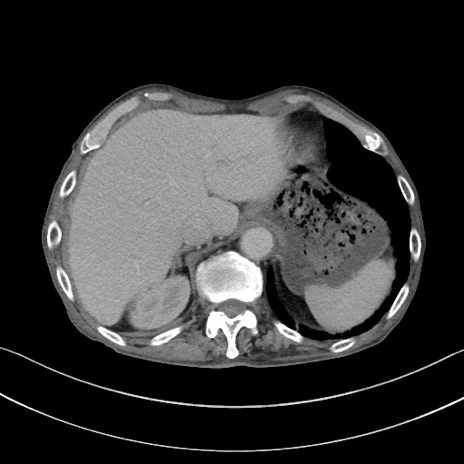

矢状断像

【症例】 70歳代男性

【主訴】右鼠径部腫瘤、疼痛

【現病歴】本日朝より上記主訴あり、受診。

【既往歴】膀胱癌にて膀胱全摘、両側尿管皮膚瘻

【データ】WBC 5600、CRP 0.56